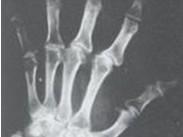

卡斯欽-貝克病(Kaschin-Beck disease)即大骨節病,是一種地方性軟骨骨關節畸形病,是以軟骨壞死為主的變形性骨關節病。多發生于兒童和少年,主要侵犯兒童和青少年的骨骼與關節系統,導致軟骨內成骨障礙、管狀骨變短和繼發的變形性關節病。致管狀長骨發育障礙,關節增粗、疼痛、肌肉松弛、萎縮和運動障礙。患者以身材矮小、短指、關節畸形、步態異常(呈典型跛行、鴨步)等為特征。本病尚有“矮人病”、“算盤子病”、“柳拐子病”等之稱。